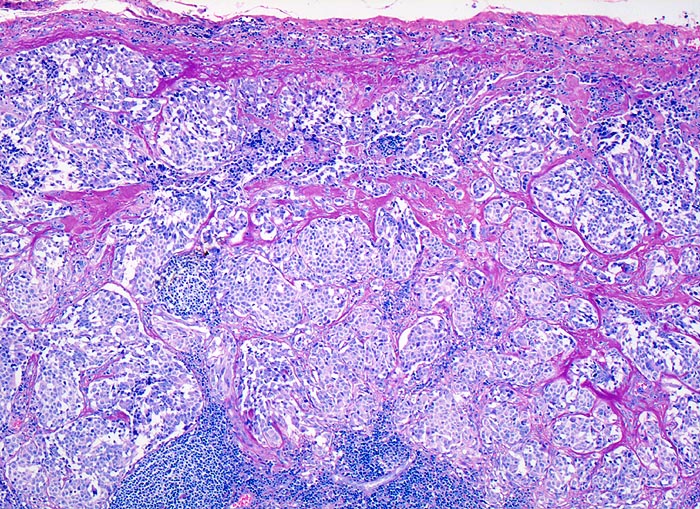

medulläres Schilddrüsenkarzinom: Lymphknotenmetastase

Spärlicher Reste von lymphatischem Gewebe unten im Bild. Tumorinfiltrat aus soliden monomorphen Zellballen umgeben von breiten Sklerosesepten.

Calcitonin in den Tumorzellen positiv.

Verschiedene Tumormetastasen können ein malignes Lymphom vortäuschen: Nasopharynxkarzinom, malignes Melanom, Seminom, Merkelzellkarzinom. Andererseits können maligne Lymphome Karzinom- oder Melanommetastasen imitieren: grosszellig anaplastische Lymphome.